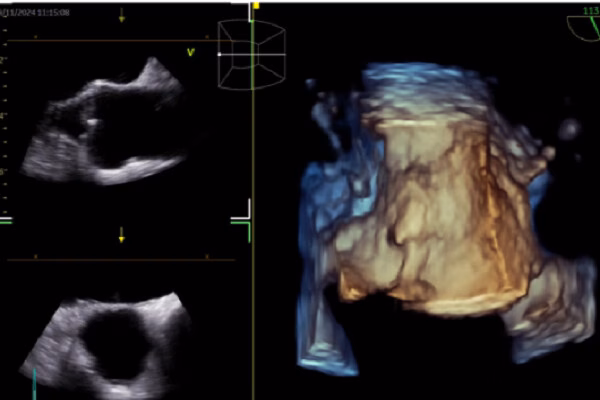

Trong ECG, AI được sử dụng để dự đoán các bệnh lý tim mạch như rung nhĩ, suy tim có phân suất tống máu giảm và hẹp van động mạch chủ. AI cũng giúp nhận diện các bất thường trong nhịp tim và cảnh báo các nguy cơ tiềm ẩn. Trong siêu âm tim, AI giúp nhận diện cấu trúc cơ tim, đo đạc tự động và hỗ trợ báo cáo và chẩn đoán. AI cũng giúp bác sĩ phân tích hình ảnh siêu âm tim một cách chính xác hơn.